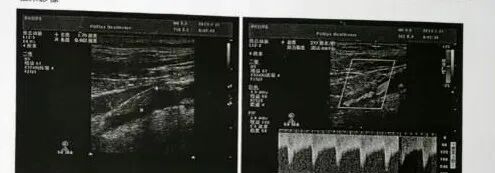

辅助检查(颈部血管彩超、CTA)

波科支架怎么样径技-弓上病例大赏|第210期·右侧颈内动脉球囊扩张术+支架植入术_https://www.jmylbn.com_新闻资讯_第6张

超声印象:

• 双侧颈动脉内膜增伴斑块形成

• 右侧颈内动脉中段狭窄